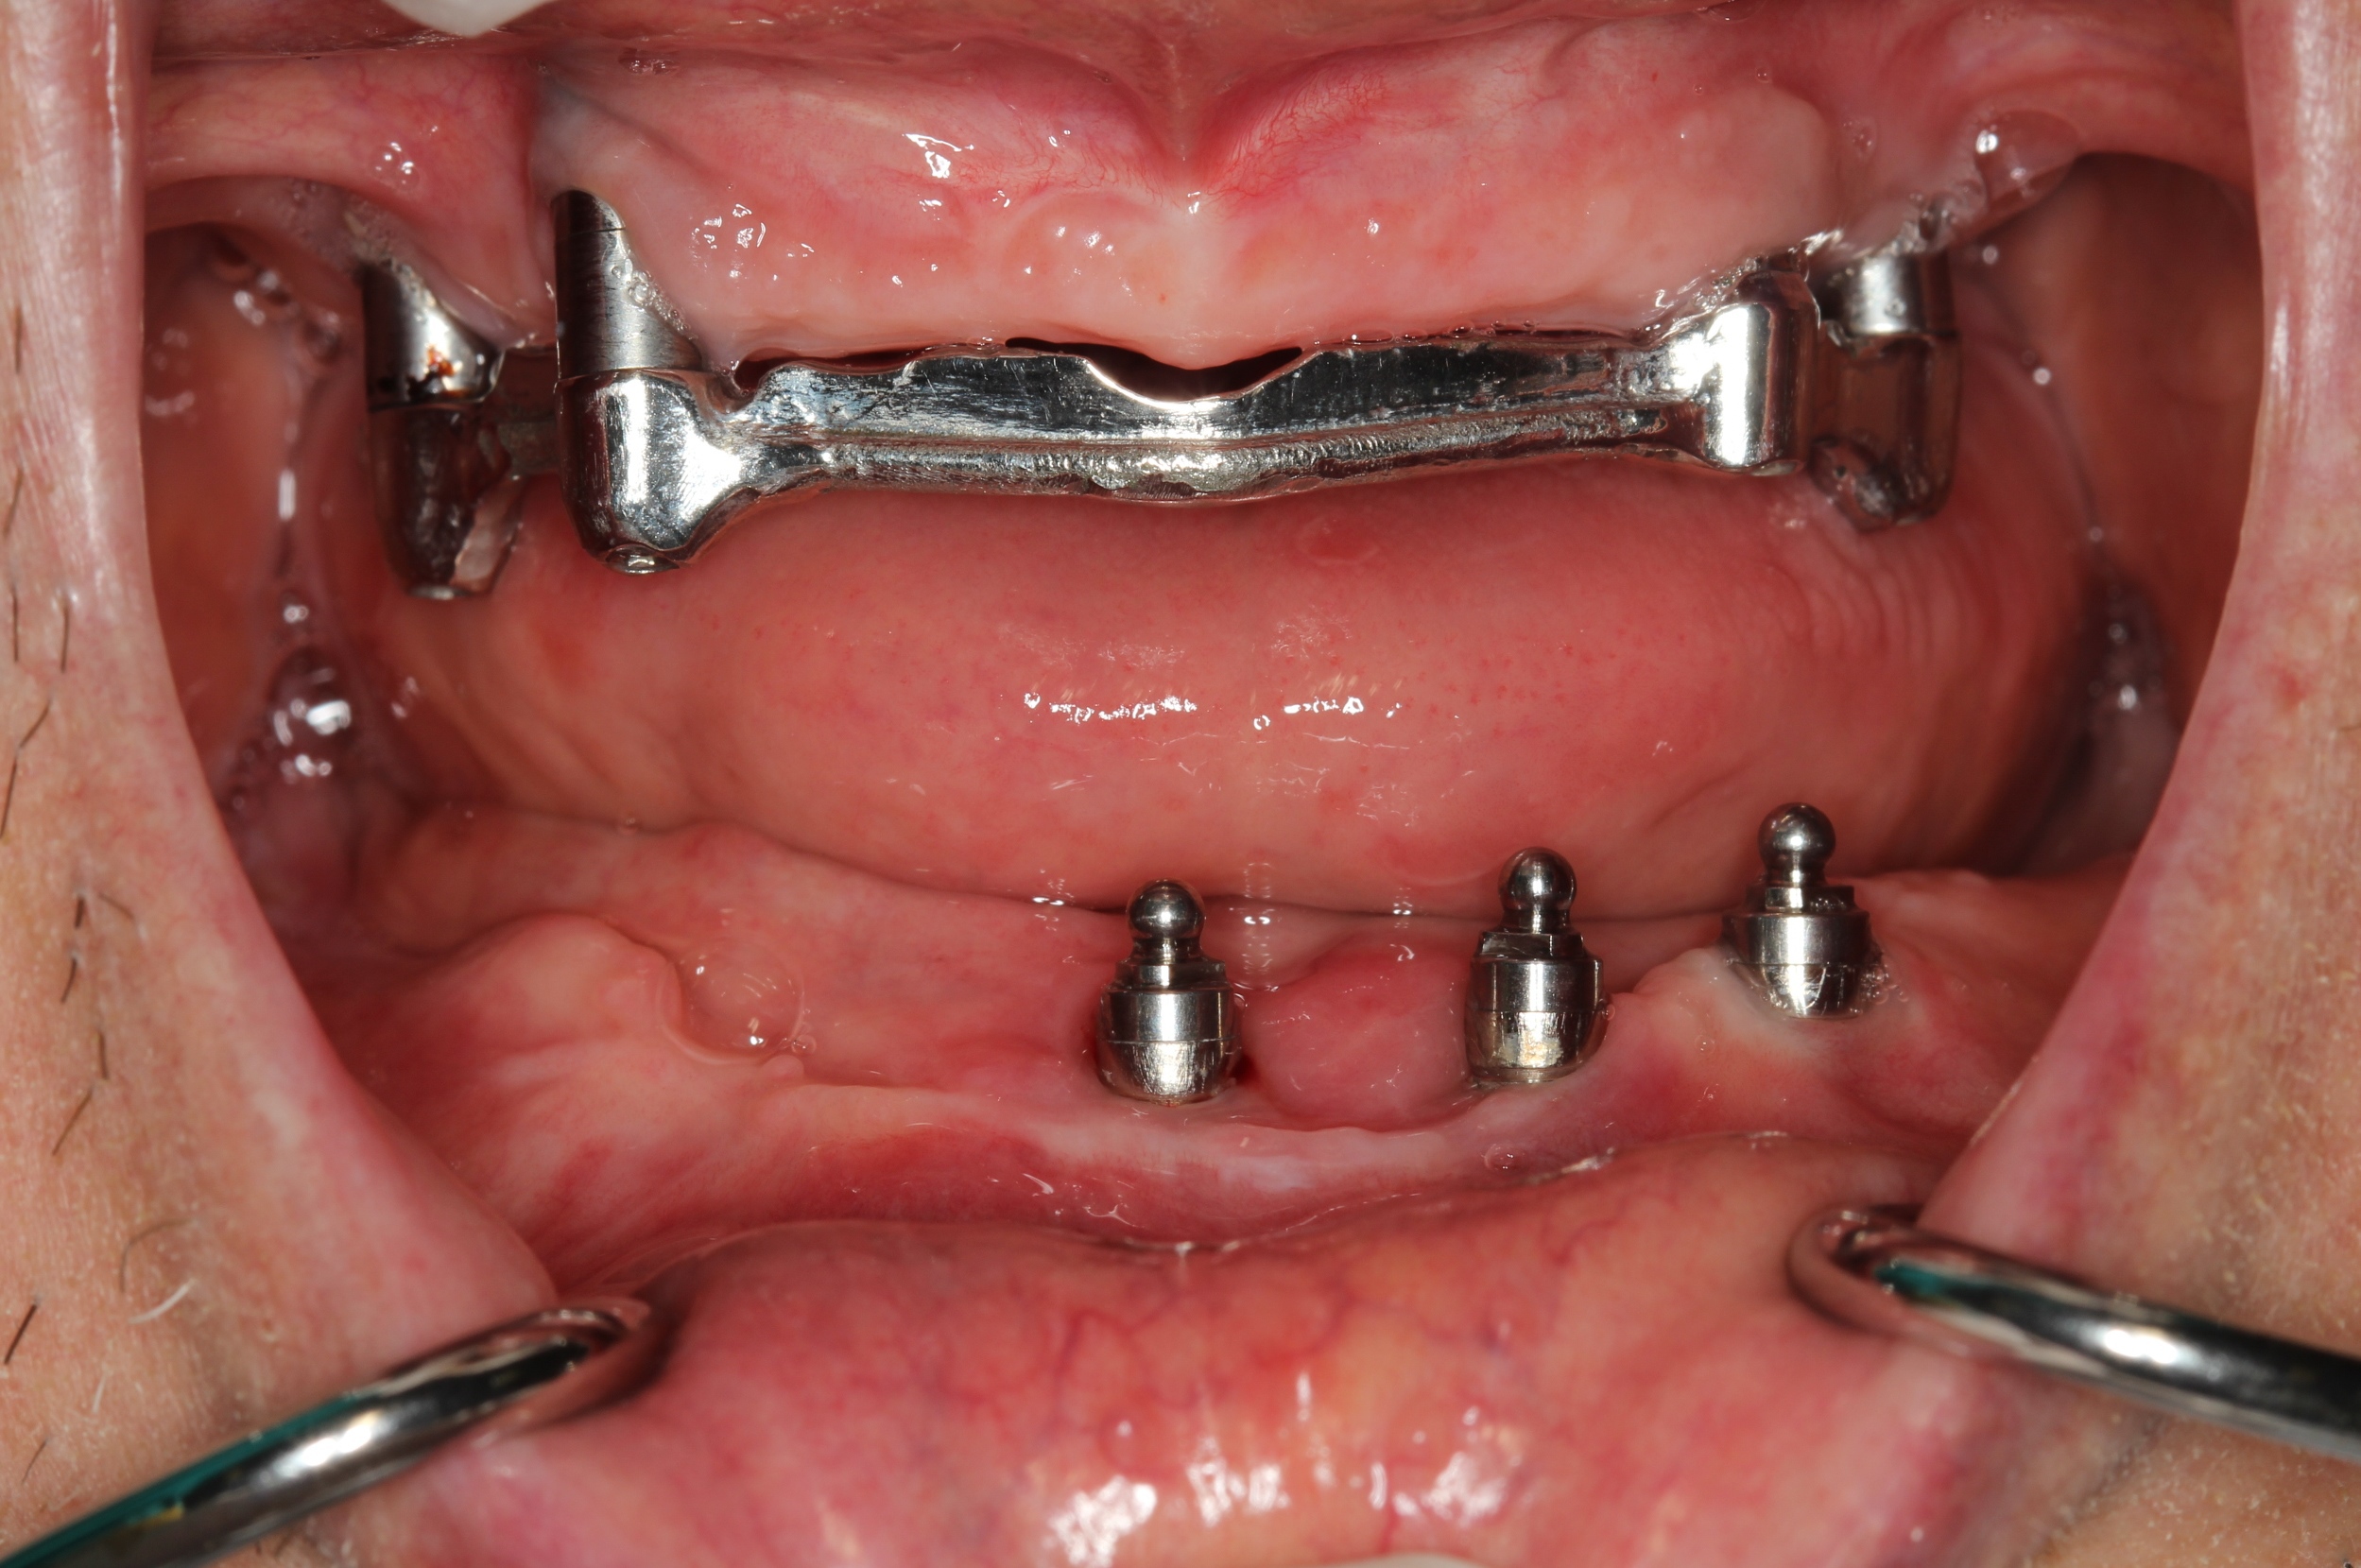

Methods: Fifty-seven years old systemically healthy non-smoker male was referred to the Department of Periodontology, Abant Izzet Baysal University from a special clinic with complaint of pain, bleeding of gums, supuration around implants and bad breath. Clinical and radiological examination revealed as peri-implantitis in mandibular anterior region (probing pocket depht (PPD) >7 mm with supuration and bleeding on probing, marginal bone loss > 1/3 implant length) for each of four implants and gingival overgrowth around maxillar implants. While removing the prosthetic abutments, one implant was lost. Peri-implant therapy included debridement of implant surfaces using titanium curettes combined with systemic antibiotics and chlorhexidine. Gingival conturing was performed using Diode laser before prosthetic rehabilitation. Oral hygiene instructions were given to the patient and peri-implant clinical parameters were recorded at 1sth, 3th, 6th and 12th months. Four months after healing of peri-implant tissues prosthetic rehabilitation was completed.

Results: There was no bleeding on probing and supuration. Radiological bone fill around implants were seen and PPD was 4 mm. During the follow periods, these results were maintained and patient had no complaints about the prosthetic rehability.